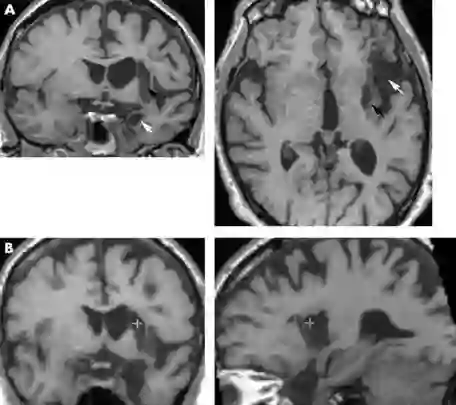

不仅如此,来自脑损伤病人的报告也向我们揭示了一些音乐与情绪之间的关系。2001年就报告了一名中风患者的案例。他是一位52岁的电台主持人,在中风前他特别喜欢听拉赫玛尼诺夫的序曲,而且每次听他都会产生一种“intense, altered emotional state or transformation”(剧烈的,情绪状态发生改变,飞升一样的体会)。他还说,只有拉赫玛尼诺夫的这一首序曲能让他有这样的感觉,其它的音乐都不行。然而在中风之后,尽管经历了漫长的康复期,这位患者的各项认知功能的受损情况都得到了缓解。测试也表明,他对音乐的知觉能力与正常人无异,可以听出音乐的韵律、节奏、具体结构等等。然而他却表示,那种“听到拉赫玛尼诺夫才有”的感觉消失得无影无踪了(Griffiths et al, 2010)。

科学家们猜测,也许是他大脑梗塞影响到了左脑岛(left insula,黑色箭头所示)和杏仁核(amygdala,白色箭头所示),导致了他不能再从拉赫玛尼诺夫的序曲中获得飞升般的快感。

脑部影像图 | 参考资料[3]